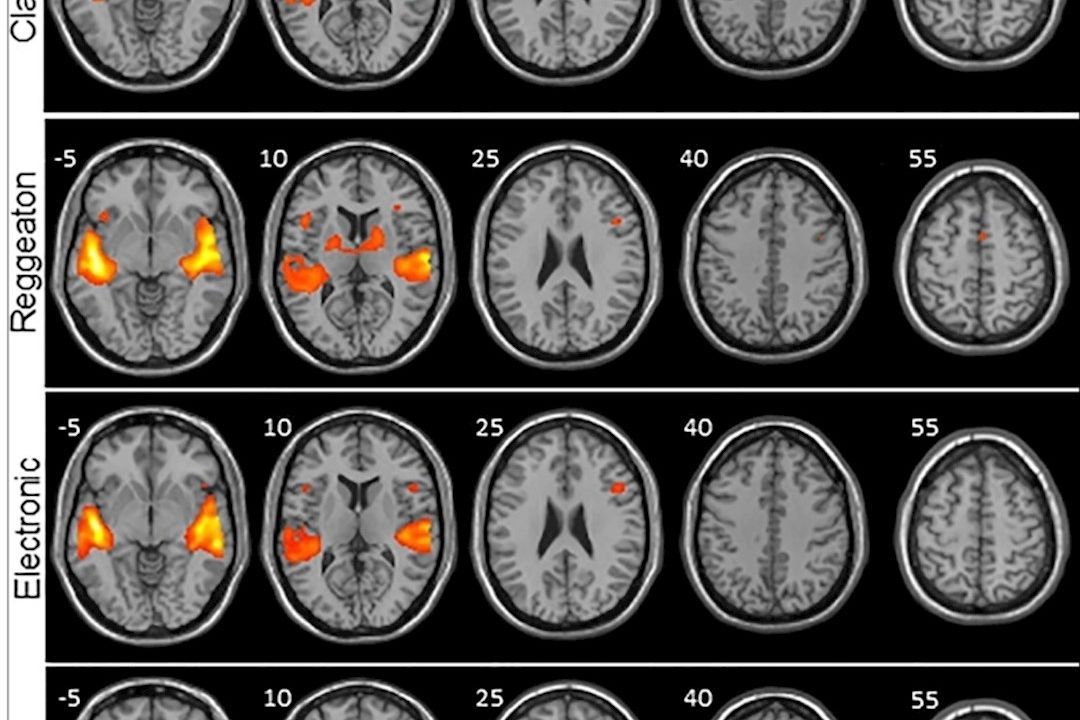

El reguetón provoca mayor actividad cerebral que escuchar clásica o folclore Sociedad EFE 26/07/2021 Frente a la música clásica, el folclore y la electrónica, el reguetón provoca una mayor activación de sonidos y movimientos